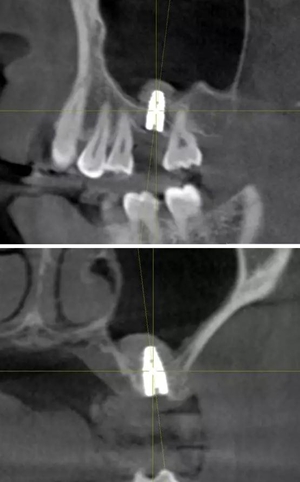

術(shù)后CBCT

提升時相關(guān)步驟可參考下面圖片

可見在完善的檢查和適當(dāng)?shù)墓ぞ哌x擇下可順利完成較復(fù)雜的上頜竇手術(shù)。